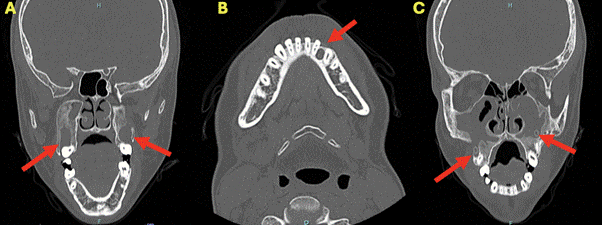

A 19-year-old male patient with a GGS diagnosis was referred in 2021 from a pediatric hospital for the therapeutic management of maxillary bone OKCs by the Maxillofacial Surgery team at San José Hospital. On clinical examination, he presented with decompression treatment cannulas for multiple OKCs previously diagnosed at the referring hospital. Treatment had started in 2019 and continued until 2021, achieving a size reduction in the OKCs for subsequent surgical management (Figure 1).

Figure 1. CT scan from 2021 showing three hypodense lesions marked with a red arrow. (A) Two bilateral hypodense lesions with a cystic appearance located in relation to both maxillary sinuses. (B) Hypodense lesion with a cystic appearance in the left parasymphyseal area. (C) Cannulas placed in both maxillary lesions.